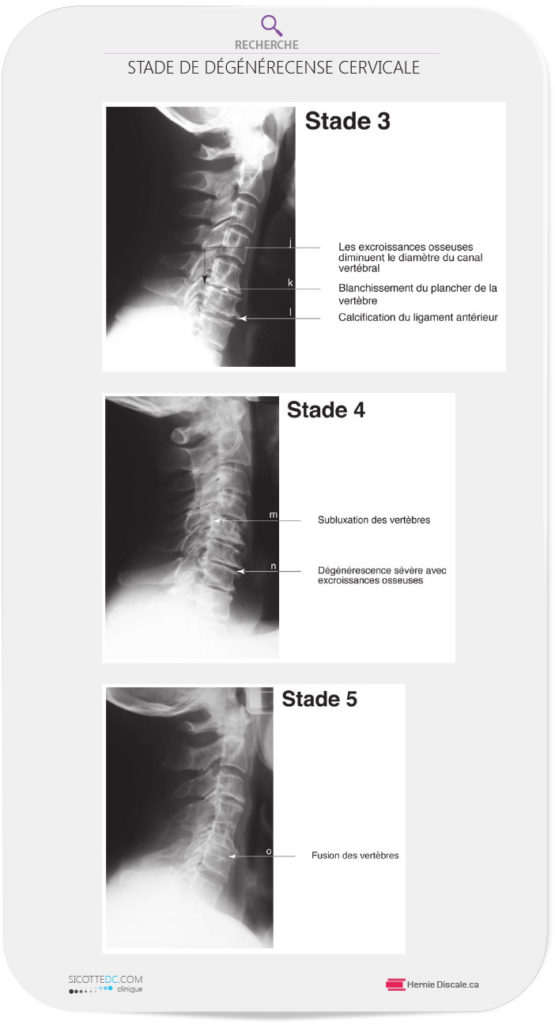

STADE 3

L’engorgement du canal vertébral par des ostéophytes sur les faces arrières des vertèbres est commun (j). La face de la vertèbre se trouve soumise à un stress anormal, ce qui est démontré par l’apparition d’une certaine blancheur juste au-dessus du disque (k). Le ligament longitudinal antérieur montre parfois des signes de calcification (I), ce qui limite le mouvement normal du cou vers l’arrière.

STADE 4

Une subluxation (déplacement mineur) significative de la vertèbre (m) apparaît. L’espace intervertébral est presque inexistant et la face de la vertèbre est déformée (n).

STADE 5

À ce stade, la fusion, est inévitable (o) et elle peut se produire à plusieurs niveaux vertébraux. La description des stades que nous venons de faire est utilisée à notre clinique lors du rapport des conclusions à la suite de votre examen. La dégénérescence est un mal permanent lorsqu’elle a débuté. Elle ne peut pas être éliminée complètement.